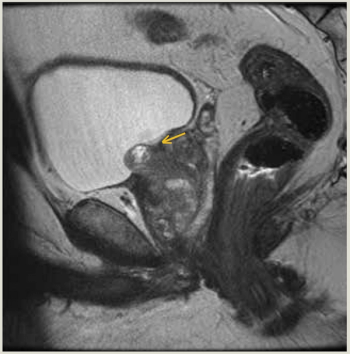

This is the case of a man, aged 56 years, who presented with urinary intermittency, frequency, urgency, and dysuria 5 months after undergoing focal laser ablation (FLA) of Gleason 3 + 4 = 7 prostate cancer (PC).

“MK,” a man aged 67 years, presented with fatigue and nausea to his primary care physician. CT staging scans confirmed the primary tumor and a suspicious left 1.2-cm inguinal lymph node but no distant metastases. MRI of the pelvis revealed complete replacement of the penis with tumor as well as invasion into the scrotum and bilateral groin soft tissue; additionally, early pubic bone invasion was present, with left groin lymphadenopathy. Biopsy verified squamous cell carcinoma of the penis, and discussion with the multidisciplinary team uroradiologist confirmed bony invasion.